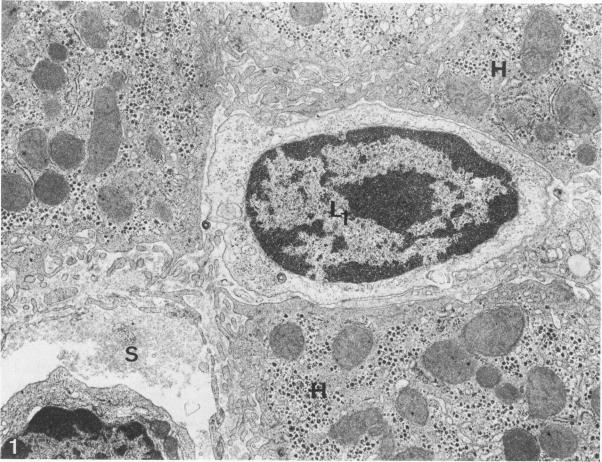

In an attempt to characterize in vivo the immune cells cytotoxic to hepatocytes in patients with chronic active hepatitis (CAH), a quantitative ultrastructural analysis of leukocytes in close contact with hepatocytes was performed in 13 patients with untreated HBsAg-negative CAH. Mononuclear phagocytes were identified by detection of endogenous peroxidase. Of the leukocytes, 8.3-4.1% were mononuclear phagocytes, 12.5-25.8% were large lymphocytes with a prominent secretory apparatus, assumed to represent mostly killer cells (T-cytotoxic cells and/or null cells), 12.2-56.8% were small lymphocytes poor in cytoplasmic organelles, and 0-45.8% were plasma cells. Patients with high serum transaminase levels had significantly more mononuclear phagocytes (P less than 0.001) and significantly fewer plasma cells (P less than 0.001) and small lymphocytes (P less than 0.001) than patients with lower disease activity. The profile of the leukocytes in contact with hepatocytes in these CAH patients suggests that mononuclear phagocyte-mediated mechanisms play an important role in hepatocyte necrosis in vivo.

为了在体内鉴定慢性活动性肝炎(CAH)患者中对肝细胞具有细胞毒性的免疫细胞,对13例未经治疗的HBsAg阴性CAH患者中与肝细胞紧密接触的白细胞进行了定量超微结构分析。通过检测内源性过氧化物酶来识别单核吞噬细胞。在白细胞中,8.3 - 4.1%是单核吞噬细胞,12.5 - 25.8%是具有突出分泌装置的大淋巴细胞,推测主要代表杀伤细胞(T细胞毒性细胞和/或裸细胞),12.2 - 56.8%是细胞质细胞器较少的小淋巴细胞,0 - 45.8%是浆细胞。血清转氨酶水平高的患者比疾病活动度较低的患者具有明显更多的单核吞噬细胞(P < 0.001),明显更少的浆细胞(P < 0.001)和小淋巴细胞(P < 0.001)。这些CAH患者中与肝细胞接触的白细胞谱表明,单核吞噬细胞介导的机制在体内肝细胞坏死中起重要作用。